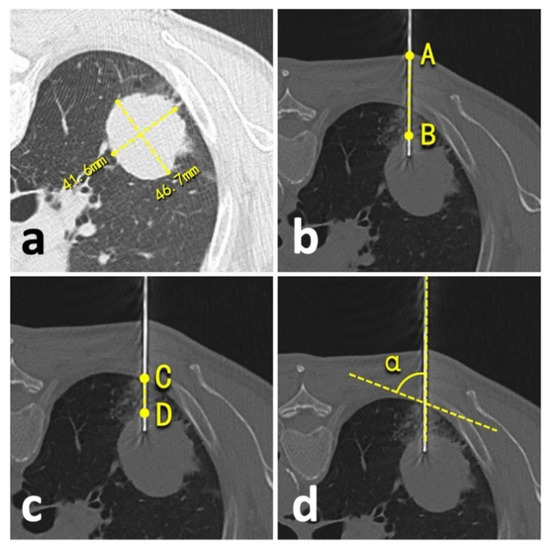

2.6. Study Goals

We compared prior emphysema history, lesion size, technical success, needle repositioning, operation time, an effective X-ray dose, complications, and biopsy accuracy between patients undergoing conventional CT- and C-arm CBCT virtual navigation-guided lung biopsies. The lesion size was defined as an average of long- and short-axis measurements in the maximum lesion section of axial CT images following the radiological statement from the Fleischner Society (Figure 3a) [19]. Technical success was defined as satisfactory biopsy materials that qualified for pathologic analysis [20]. The needle repositioning was defined as the pull-back adjustment or re-puncture when the needle tip did not reach the planning target [5,6]. During the procedure, operation time was recorded from the start of the initial CT/CBCT scan to the end of the post-biopsy CT/CBCT scan. The effective dose of conventional CT was calculated by using a dose-linear product (DLP)*κ-factor and fluoroscopy/CBCT by using a dose-area product (DAP)*dose conversion coefficient [21]. For conventional chest CT, κ-factor was 0.0146 mSv/mGy*cm [22]. For chest fluoroscopy/CBCT of the Artis system, the dose conversion coefficient was 0.0017 mSv/μGy*m2 [10,14]. The accurate biopsy was defined as the biopsy pathological result that was: 1. confirmed by the following surgery; or 2. supported by subsequent clinical course for at least one year (e.g., growth or metastasis of malignancies, stable or regression of benign lesions, etc.) [6,7,10,23].

The biopsy-related complications were collected and classified from Grade-A to -E under the standards of the Society of Interventional Radiology [24]. A minor complication was defined as Grade-A or -B complication, and a major complication as Grade-C to -E complication [24]. Besides this, the risk factors of complication were comprehensively explored, including prior emphysema history, patient position during the biopsy, lesion size, needle repositioning, lesion-skin distance along the needle path (from lesion border to skin) (Figure 3b), lesion-pleural distance along the needle path (from lesion border to pleura) (Figure 3c), needle-pleural angle (Figure 3d), and the number of obtained samples [4,5,19,20,23]. Two independent radiologists performed all measurements (LY and YW, with 23- and 2-year experience in thoracic radiology, respectively), and the average of the measurements was involved in the final analysis.

Figure 3. Illustration of quantitative measurements. (a), lesion size; (b), lesion-skin distance; (c), lesion-pleural distance; (d), needle-pleural angle.